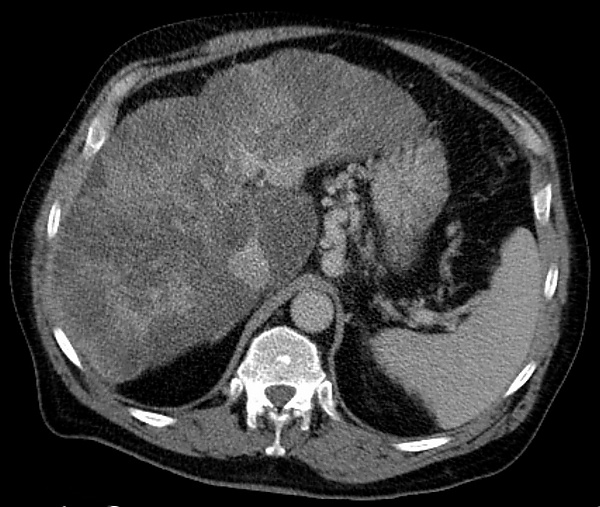

Варикозное расширение вен желудка — это расширение вен в слизистой оболочке желудка, которое может вызывать опасное для жизни кровотечения в верхних отделах желудочно-кишечного тракта[1]. Оно чаще всего встречается у пациентов с портальной гипертензией или повышенным давлением в системе воротной вены, что может быть осложнением цирроза печени. Варикозное расширение вен желудка также может быть обнаружено у пациентов с тромбозом селезеночной вены, в которую впадают короткие желудочные вены, дренирующие дно желудка. Последнее может быть осложнением острого панкреатита, рака поджелудочной железы или других опухолей брюшной полости, а также гепатита С. Варикозное расширение вен желудка и связанные с ним кровотечения являются потенциальным осложнением шистосомоза, возникающего в результате портальной гипертензии[1].

Во-вторых, у пациентов с острым панкреатитом может развиться варикозное расширение вен желудка как осложнение тромбоза селезеночной вене. Анатомически селезеночная вена расположена над поджелудочной железой. Воспаление или рак поджелудочной железы могут привести к образованию тромба в селезеночной вене. Поскольку короткие желудочные вены дна желудка впадают в селезеночную вену, тромбоз селезеночной вены приводит к повышению давления и закупорке коротких вен, что приводит к варикозному расширению вен дна желудка[4].